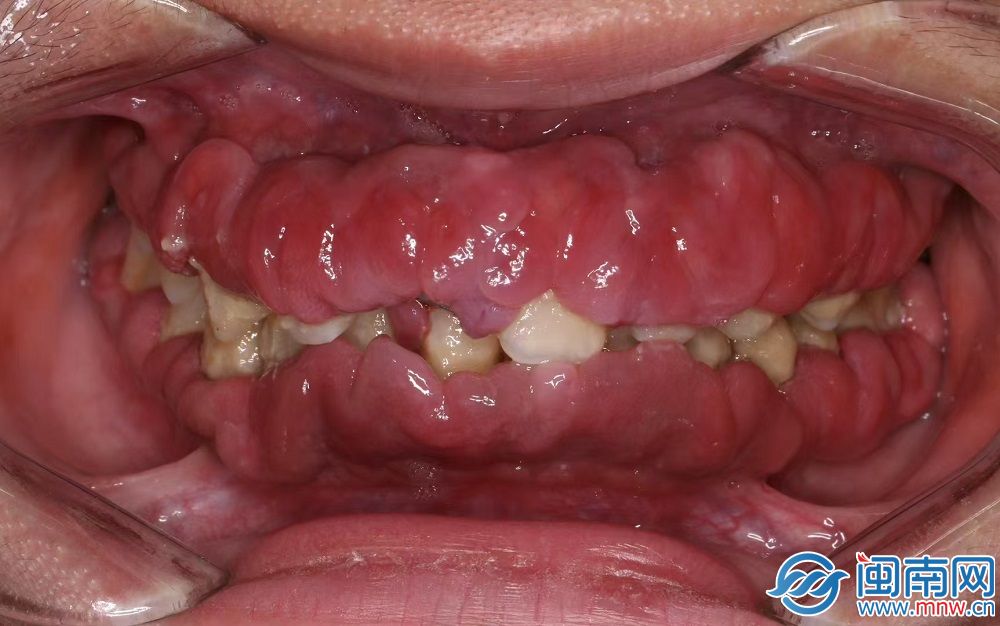

陳醫(yī)生介紹,小強的牙齦紅腫、圓鈍,不是緊貼著牙齒,而是松松垮垮,看起來“胖嘟嘟”的,暗紅色的牙齦包裹著牙齒,幾乎看不到牙齒。仔細(xì)看,牙齒被一層厚厚的軟垢包繞著,有些牙已經(jīng)開始松動。

“胖嘟嘟”的牙齦包裹住牙齒(醫(yī)生供圖)